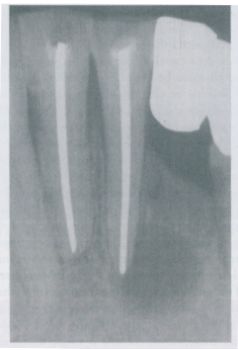

20.下圖根尖放射線影像中之病變,其鑑別診斷最不可能為下列何者? (A)radicular cyst(B)lateral periodontal cyst(C)odontogenic keratocyst(D)globulomaxillary cyst